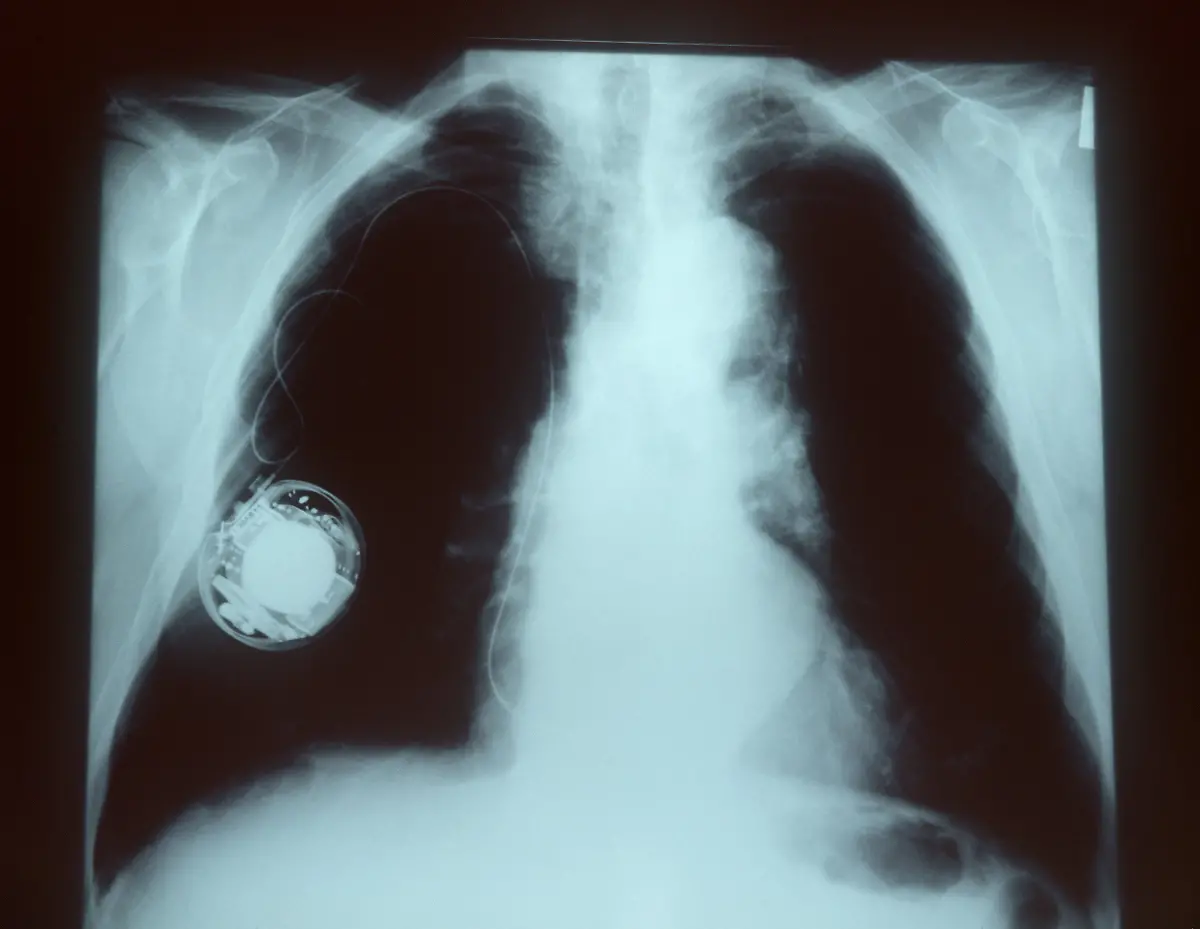

Geräte werden immer kleinerHerzschrittmacher retten Tausende Leben

Am 8. Oktober 1958 wird erstmals ein Herzschrittmacher in einen menschlichen Körper eingesetzt. Seitdem helfen die kleinen Kisten dabei, das Herz wieder im richtigen Takt schlagen zu lassen - und retten damit Leben.